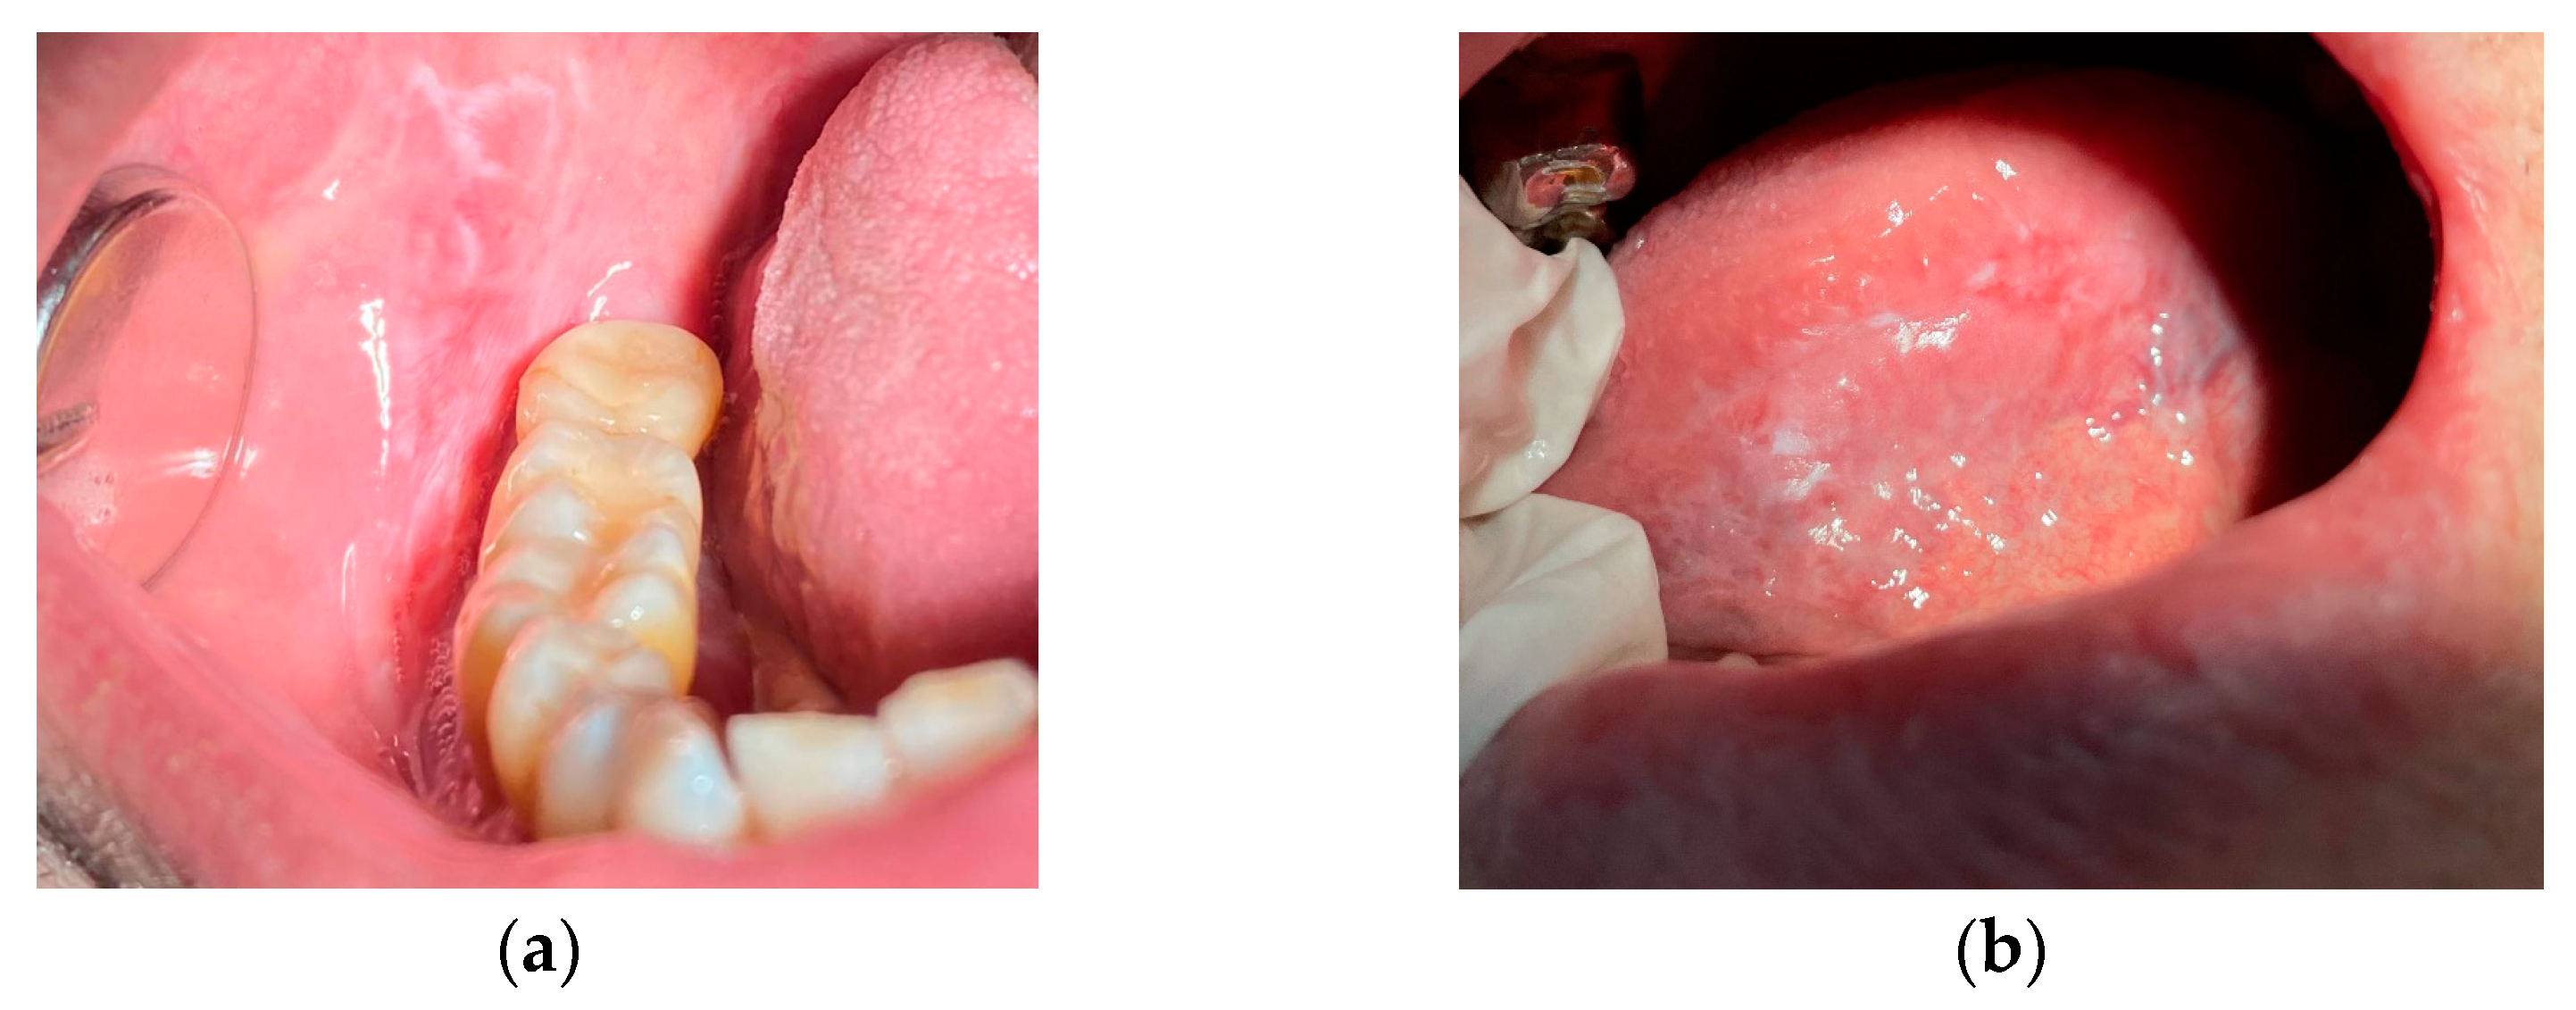

Examples of images of lesions are shown in Figure 1.

Figure 1.

Examples of images of the lesion areas of the oral cavity: an area of hyperkeratosis on the surface of the buccal mucosa (a) and on the ventrolateral surface of the tongue (b).